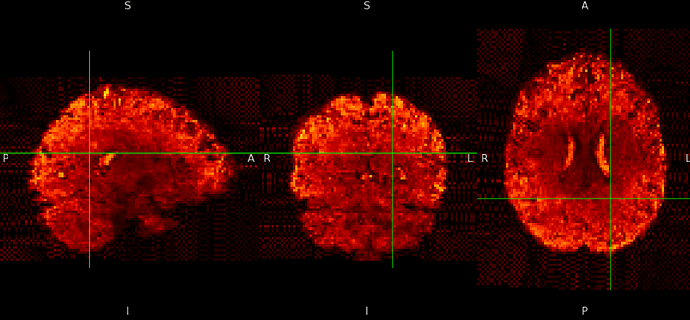

The pattern is not present in the raw data. It is not present either in the fmriprep native space. For example,

SE sequence in native:

ME sequence in native: